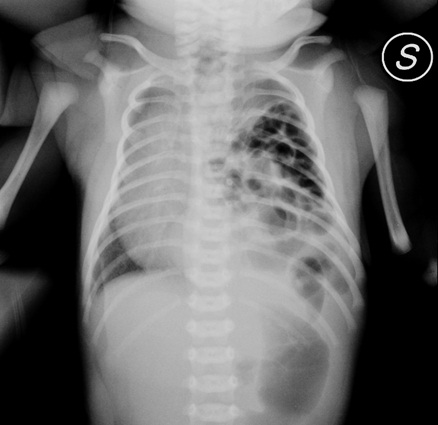

Passo successivo: e se si trattasse di un�ernia

diaframmatica non riconosciuta all�indagine morfologica?

A sostegno del nostro secondo sospetto, richiediamo una radiografia del torace: �risalita dell'intestino nell'emitorace di sinistra� (Figura 1).

Figura 1.

Ci avevamo visto giusto! Non c�� tempo da perdere: � necessario ripristinare la corretta anatomia del nostro piccolo paziente e in accordo con i nostri dirimpettai di reparto (meglio identificati come chirurghi) accompagniamo F. in sala operatoria.